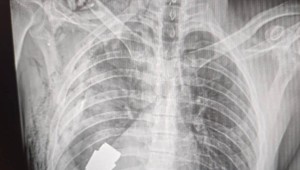

BRATISLAVA / O ďalších detailoch náročnej operácie pri vyberaní nevybuchnutej strely z granátometu sme sa rozprávali s Petrom. Jeho tvár vám nemôžeme ukázať, pretože pôsobí na Ukrajine a je súčasťou tímov taktickej medicíny. Rozhovor urobila reportérka Marika Dulaiová.